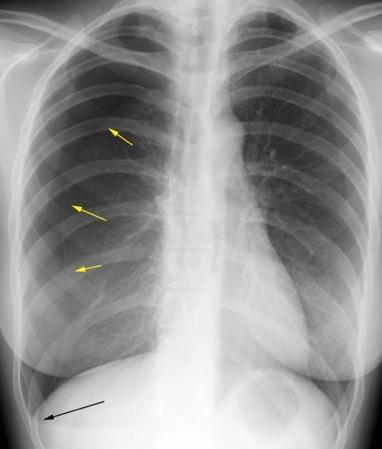

91. NEUMOTÓRAX EN ESPIRACIÓN

Visualización de la pleura visceral separada de la parietal por aire Borde externo Convexo Localización: Ápex pulmonar

M. Bradley et al. Value of routine expiratory chest films in the diagnosis of pneumothorax.Arch Emerg Med.1991, F. Schramel, et al. Expiratory chest radiographs do not improve visibility of small apical pneumothoraces by enhanced contrast.Eur Respir J. 1996,

Sospecha de neumotórax Neumotórax